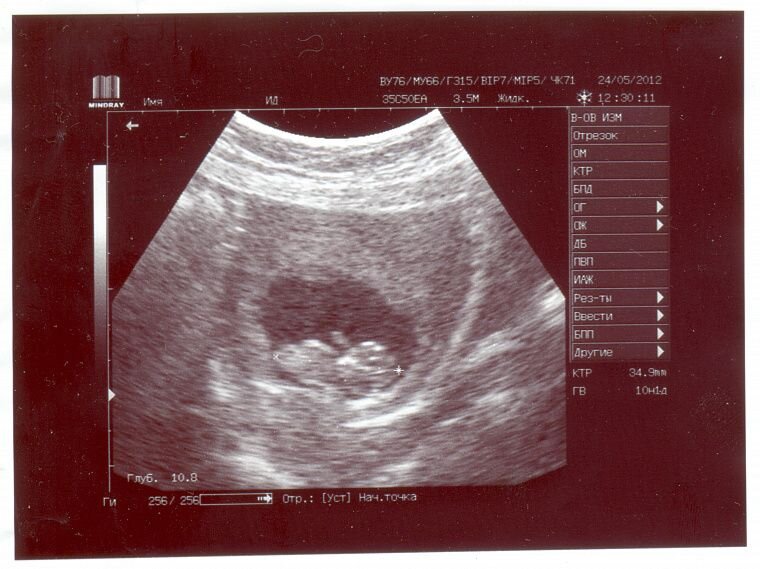

Чем опасны ошибки во время УЗИ

Рано или поздно врач ультразвуковой диагностики может ошибиться и поставить неправильный диагноз. Тем самым он подвергает опасности здоровье не только беременной женщины, но и её ребёнка.

Со мной тоже произошёл очень неприятный случай, когда я вынашивала ребёнка. В третьем триместре я прошла плановое УЗИ. Врач, закончив осмотр, ничего не сказал, отдал мне заключение и отправил за дверь. Я взглянула на его равнодушное лицо и поняла, что ему всё равно, он даже ребёнка мне на экране не показал.

В коридоре я села на скамейку читать диагноз. В заключении врач УЗИ написал «Преждевременное старение плаценты и фетоплацентарная недостаточность». У меня началась паника: я знала, к чему это может привести. Я так расстроилась, что еле сдерживала слёзы. В конце концов, не каждый день такое узнаёшь. Но я решила взять себя в руки и успокоиться, потому что стресс и нервное напряжение очень влияют на беременность, и из-за этого могут начаться преждевременные роды. Я – будущая мама, и в ответе за жизнь и здоровье своего малыша.

Госпитализироваться мне было никак нельзя: муж только вышел из отпуска, денег у нас было мало, а ежемесячный платёж по ипотеке никто не отменял. Поэтому я решила сходить повторно на УЗИ и пройти допплерографию платно. Если мой диагноз подтвердится, то лягу в больницу, другого выбора нет: гипоксия и недостаток питания опасны для здоровья малыша, он будет отставать во внутриутробном развитии и может даже погибнуть.

-2

Я нашла хорошую клинику и отличного платного специалиста. Врач меня внимательно выслушал, посмотрел заключение и начал исследование. Проведя осмотр, он уверенно сообщил, что никакого старения плаценты нет – мне поставили неправильный диагноз. Потом он провёл допплерографию – это исследование, при котором оценивают кровоток малыша в разных органах и системах. Если допплер показал, что сосуды пуповины без патологии, то с ребёнком всё хорошо, и он не страдает от гипоксии. У нас всё было в пределах нормы. Я поблагодарила врача и вышла с заключением из кабинета абсолютно счастливая.